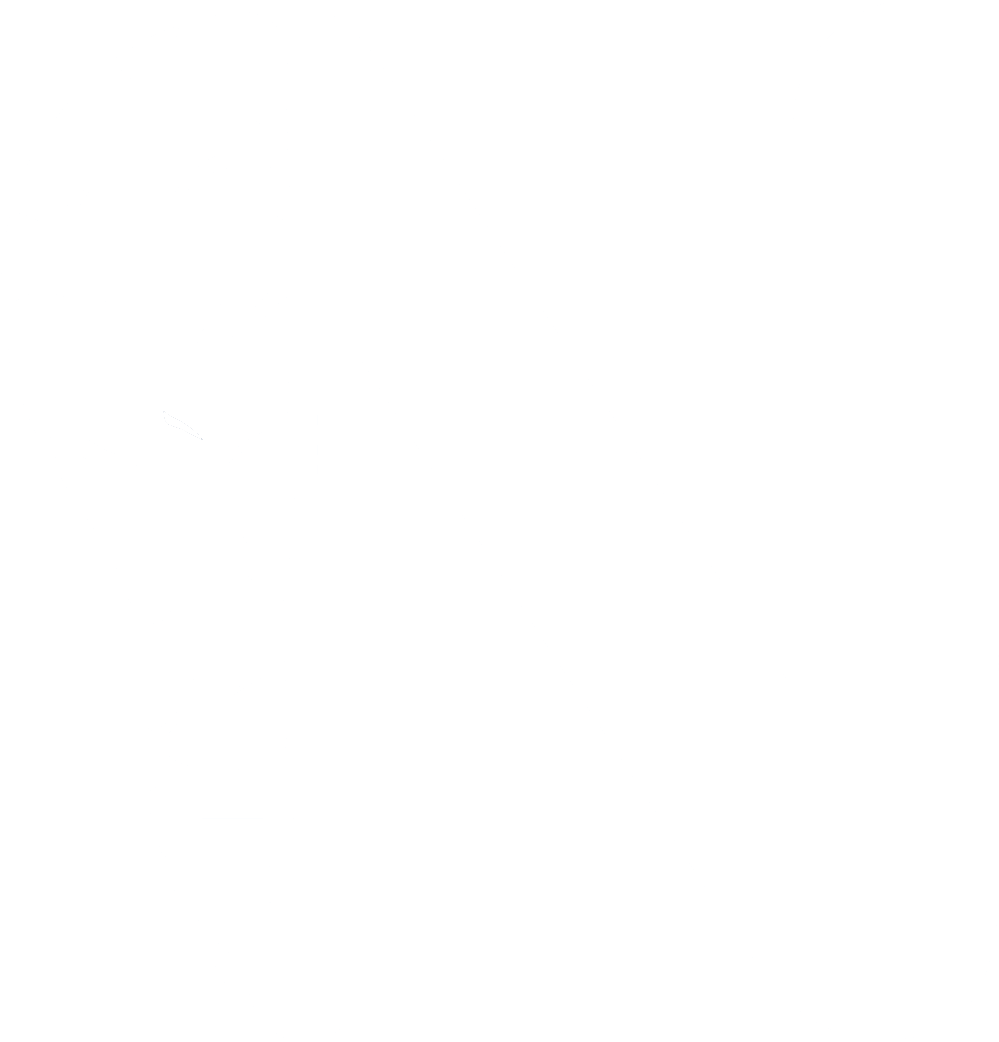

One of the most impactful applications of AI has been the detection and classification of neurological disorders. For example, advanced models can now analyze T2-weighted MR images to identify Alzheimer’s disease with accuracy rates approaching 98%.

Figure 1 General framework for Alzheimer’s disease detection using AI (Subasi 2020)